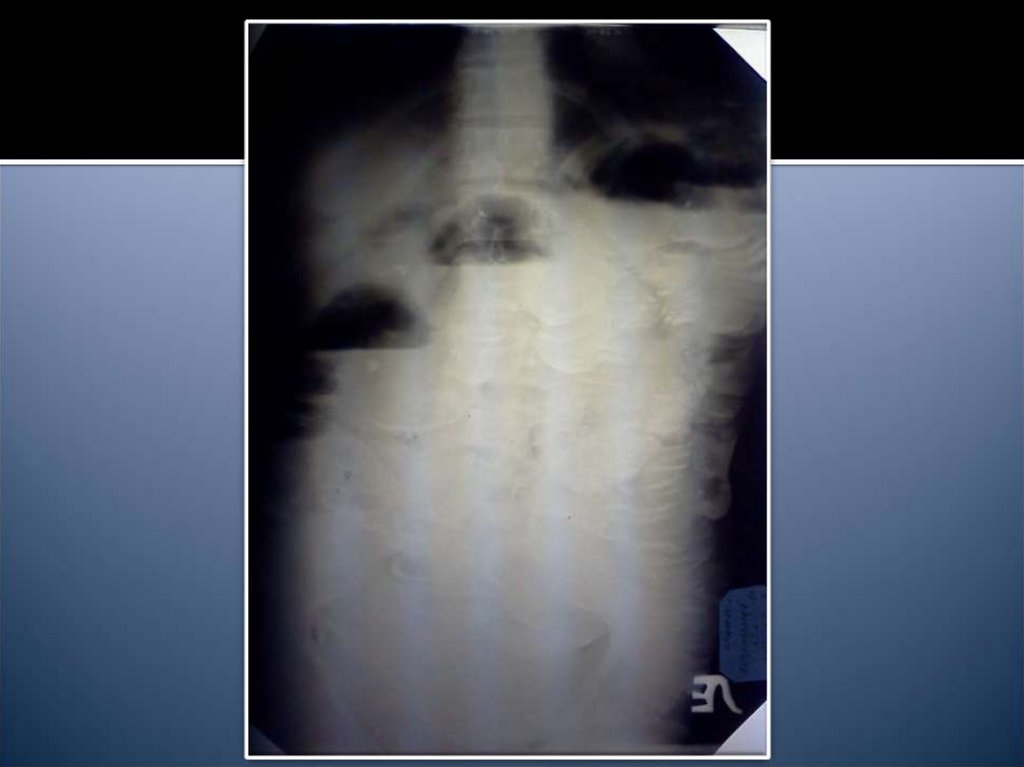

14. Рентгенологические признаки

Чаши Клойбера

Симптом Кивуля (аркады)

Проба Шварца

Пневматоз петель кишечника